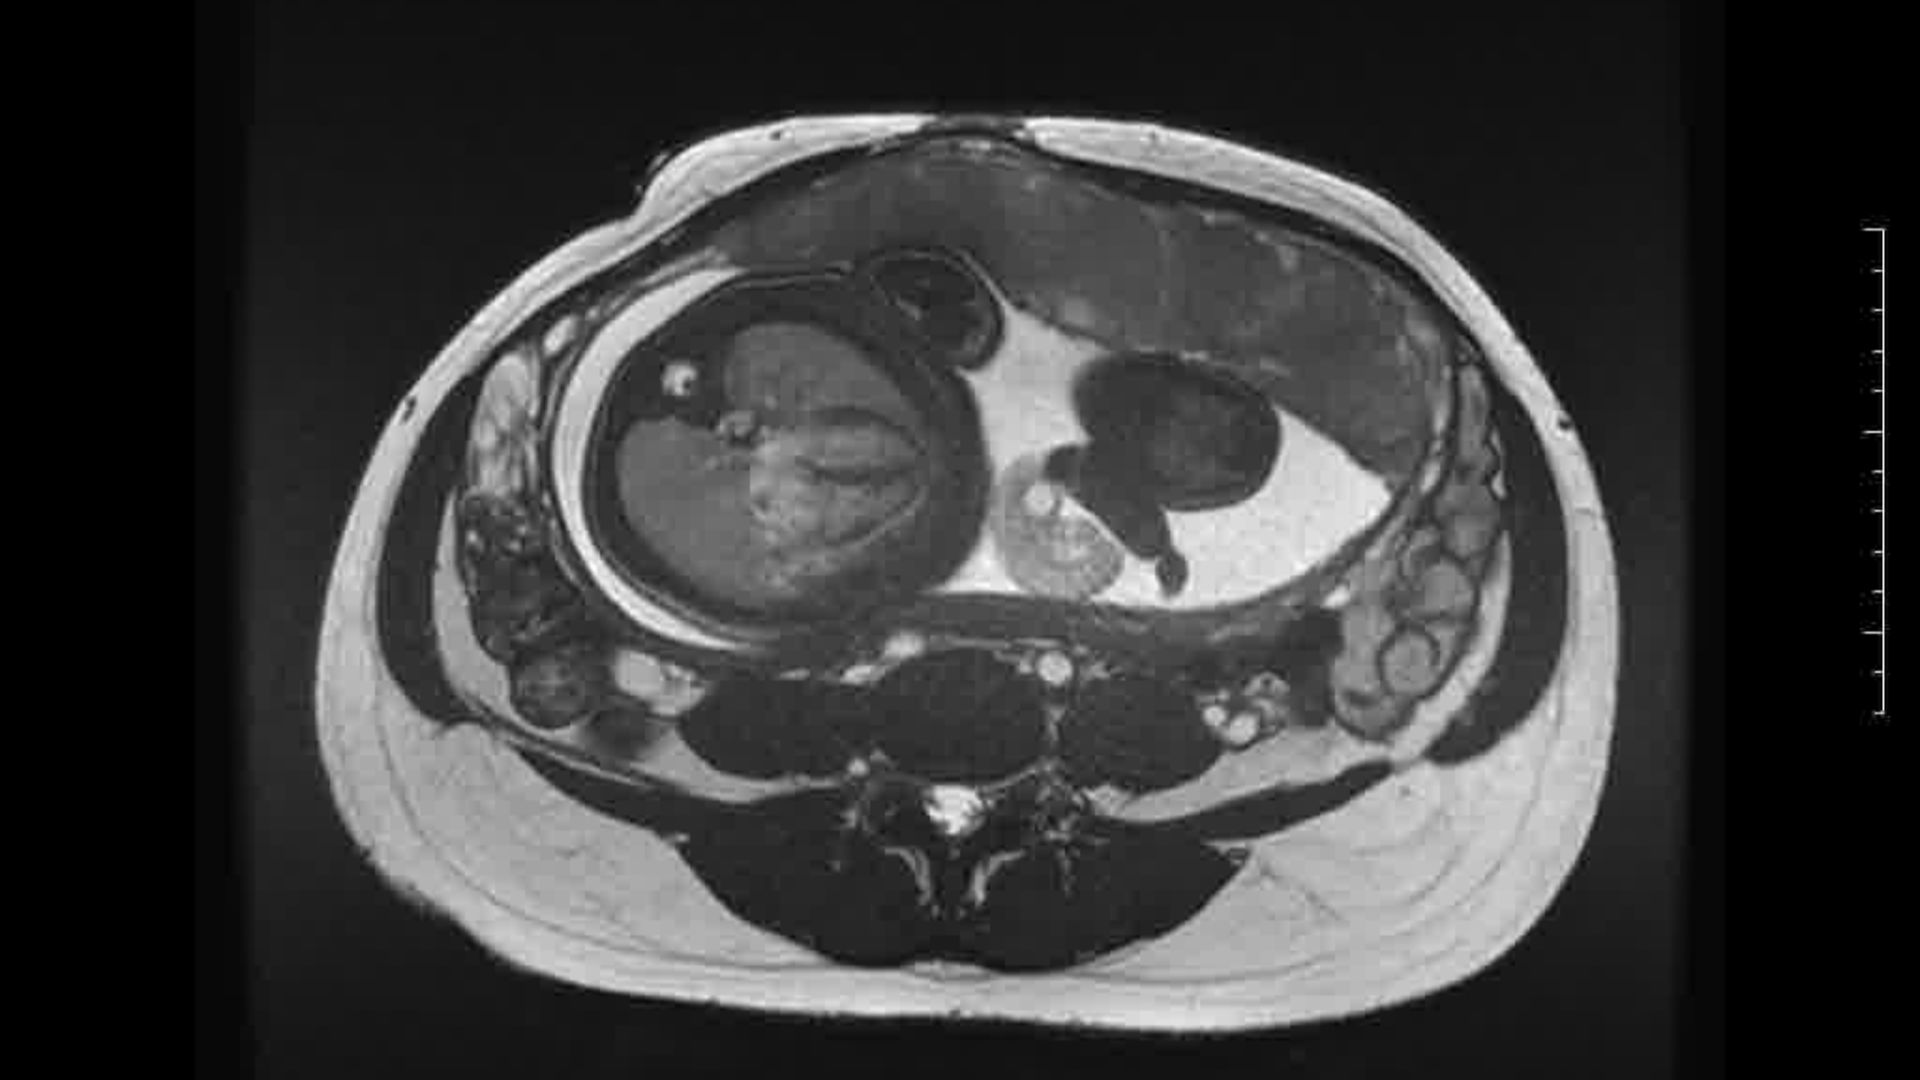

L’Université Paris Cité franchit une nouvelle étape dans le domaine de l’imagerie médicale anténatale avec l’acquisition d’un système d’Imagerie par Résonance Magnétique (IRM) 1,5T ARTIST™ de GE HealthCare. Cet équipement de pointe renforce les capacités de la Plateforme LUMIERE à l’hôpital Necker-Enfants malades, plateforme intégrée de soins, de recherche clinique et d’enseignement en imagerie médicale de la femme enceinte, du fœtus et du placenta.

L’acquisition de cette nouvelle IRM s’inscrit dans le cadre du protocole de recherche « LUMIERE SUR LE FETUS », dont les objectifs sont d’améliorer la prise en charge des pathologies anténatales, d’affiner leur pronostic et de contribuer à la réduction de la morbidité et de la mortalité à court, moyen et long terme. Cette acquisition a été rendue possible grâce au don exceptionnel de la Fondation LUMIERE d’un montant de 250k euros ainsi qu’au soutien de l’Université Paris Cité à hauteur de 670k euros.

Depuis 2020, la Plateforme LUMIERE offre aux femmes enceintes volontaires, entre 16 et 36 semaines d’aménorrhée et suivies à l’hôpital Necker-Enfants malades, la possibilité de participer activement à l’avancée de la recherche en médecine fœtale, tout en bénéficiant d’une IRM fœtale au cours de leur grossesse, réalisée dans un cadre sécurisé et encadré.

L’inclusion de ces patientes, depuis leur accueil jusqu’à la réalisation des examens d’imagerie, puis l’analyse des images et l’interprétation des résultats par des équipes expertes, enrichit une base de données structurée, unique au monde, au service de la recherche et de l’innovation en imagerie anténatale et en médecine fœtale.